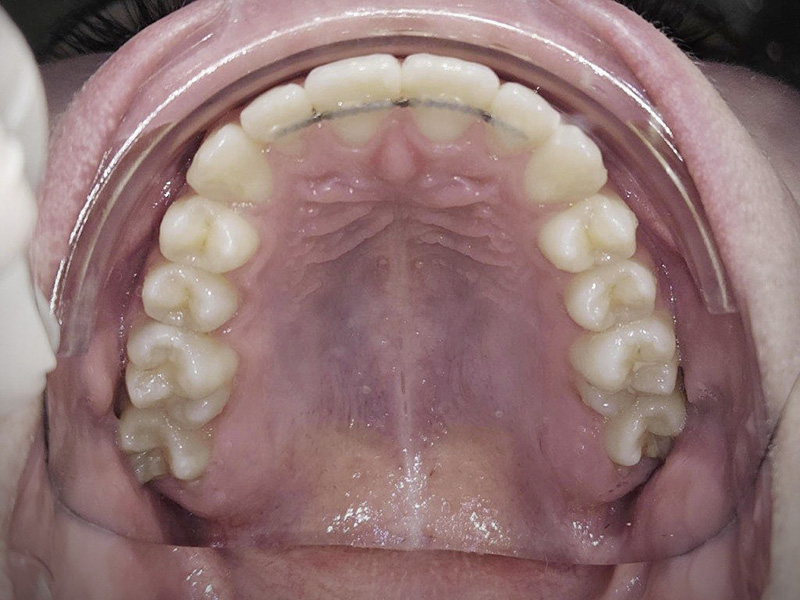

- >Contention

Après un traitement d’orthodontie (par bagues ou par gouttières), les dents mettent une année pour retrouver une certaine stabilité.

Nous installons donc des systèmes pour que les dents bougent le moins possibles, un peu comme un tuteur avec une plante.

Malgré la contention, les dents peuvent tout de même se déplacer de nouveau, ce qui nécessite une surveillance au cabinet d’au moins 3 ans.

Au cabinet, nous utilisons très souvent la technologie MEMOTAIN.

Il s’agit d’un fil de contention ajusté, confortable, individualisé grâce à l’empreinte optique et conçu sur mesure au laboratoire afin de s’adapter de manière personnalisée à chacun.